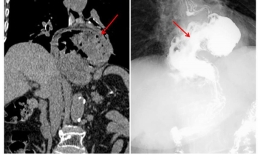

与此同时,安医大一附院肝胆胰外科谢青松教授也受邀前来,分别指导外一科开展“腹腔镜下胰体尾+脾脏切除术”,在外二科指导开展“腹腔镜下左肝外叶切除+胆总管探查术”。这些手术均属于肝胆胰外科领域的复杂四级手术,具有复杂性和严重并发症发生的风险,在安医一附院专家的精准指导下,患者术后均顺利康复。

安医大一附院肝胆胰外科谢青松教授指导开展

“腹腔镜下胰体尾+脾脏切除术”

“腹腔镜下左肝外叶切除+胆总管探查术”